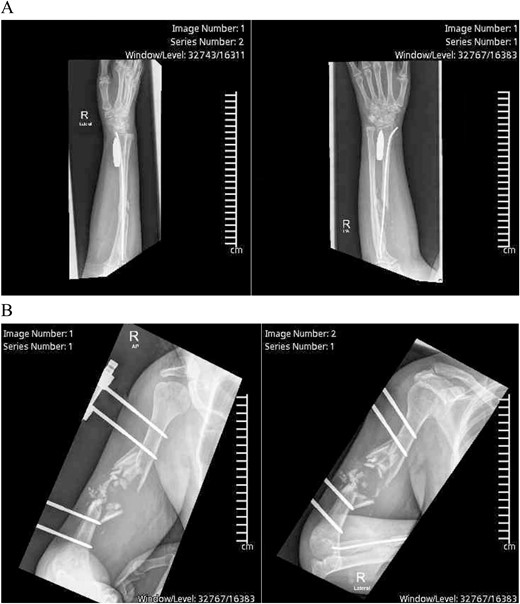

Exploration revealed severe adhesions of radial, median, and ulnar nerves in the proximal 2/3rd third of the arm, adhesions were lesser as the nerves coursed distally in the lower arm and proximal forearm. The radial nerve was completely severed with a marked gap between the distal and proximal ends (Fig. 2). Muscle bellies lying along the bullet tract, at the posterior compartment of arm and volar forearm were charred, fibrotic and replaced by fat. Complete decompression of the peripheral nerves in addition to bullet extraction was performed by Plastic Surgery, with a plan for tendon transfer in regard to the severed radial nerve later on. (Figs 3 and 4) During the surgery, the brachial artery was found severely attenuated, matted to the venae comitantes, and stuck to the bone at fracture site without any recognizable plane in-between, and during adhesiolysis, the artery was inadvertently injured. It was repaired using interposition reversed saphenous vein graft by Vascular Surgery. The patient’s postoperative period was uneventful, with good distal capillary refill and pain control. She was discharged 8 days after the surgery and regularly followed in the outpatient clinic and the hand occupational therapy unit. 3 months follow-up showed significant improvement in sensory symptoms and minimal improvement in motor function.

Intraoperative X-ray showing the final position of the bullet on the volar aspect of the radius.